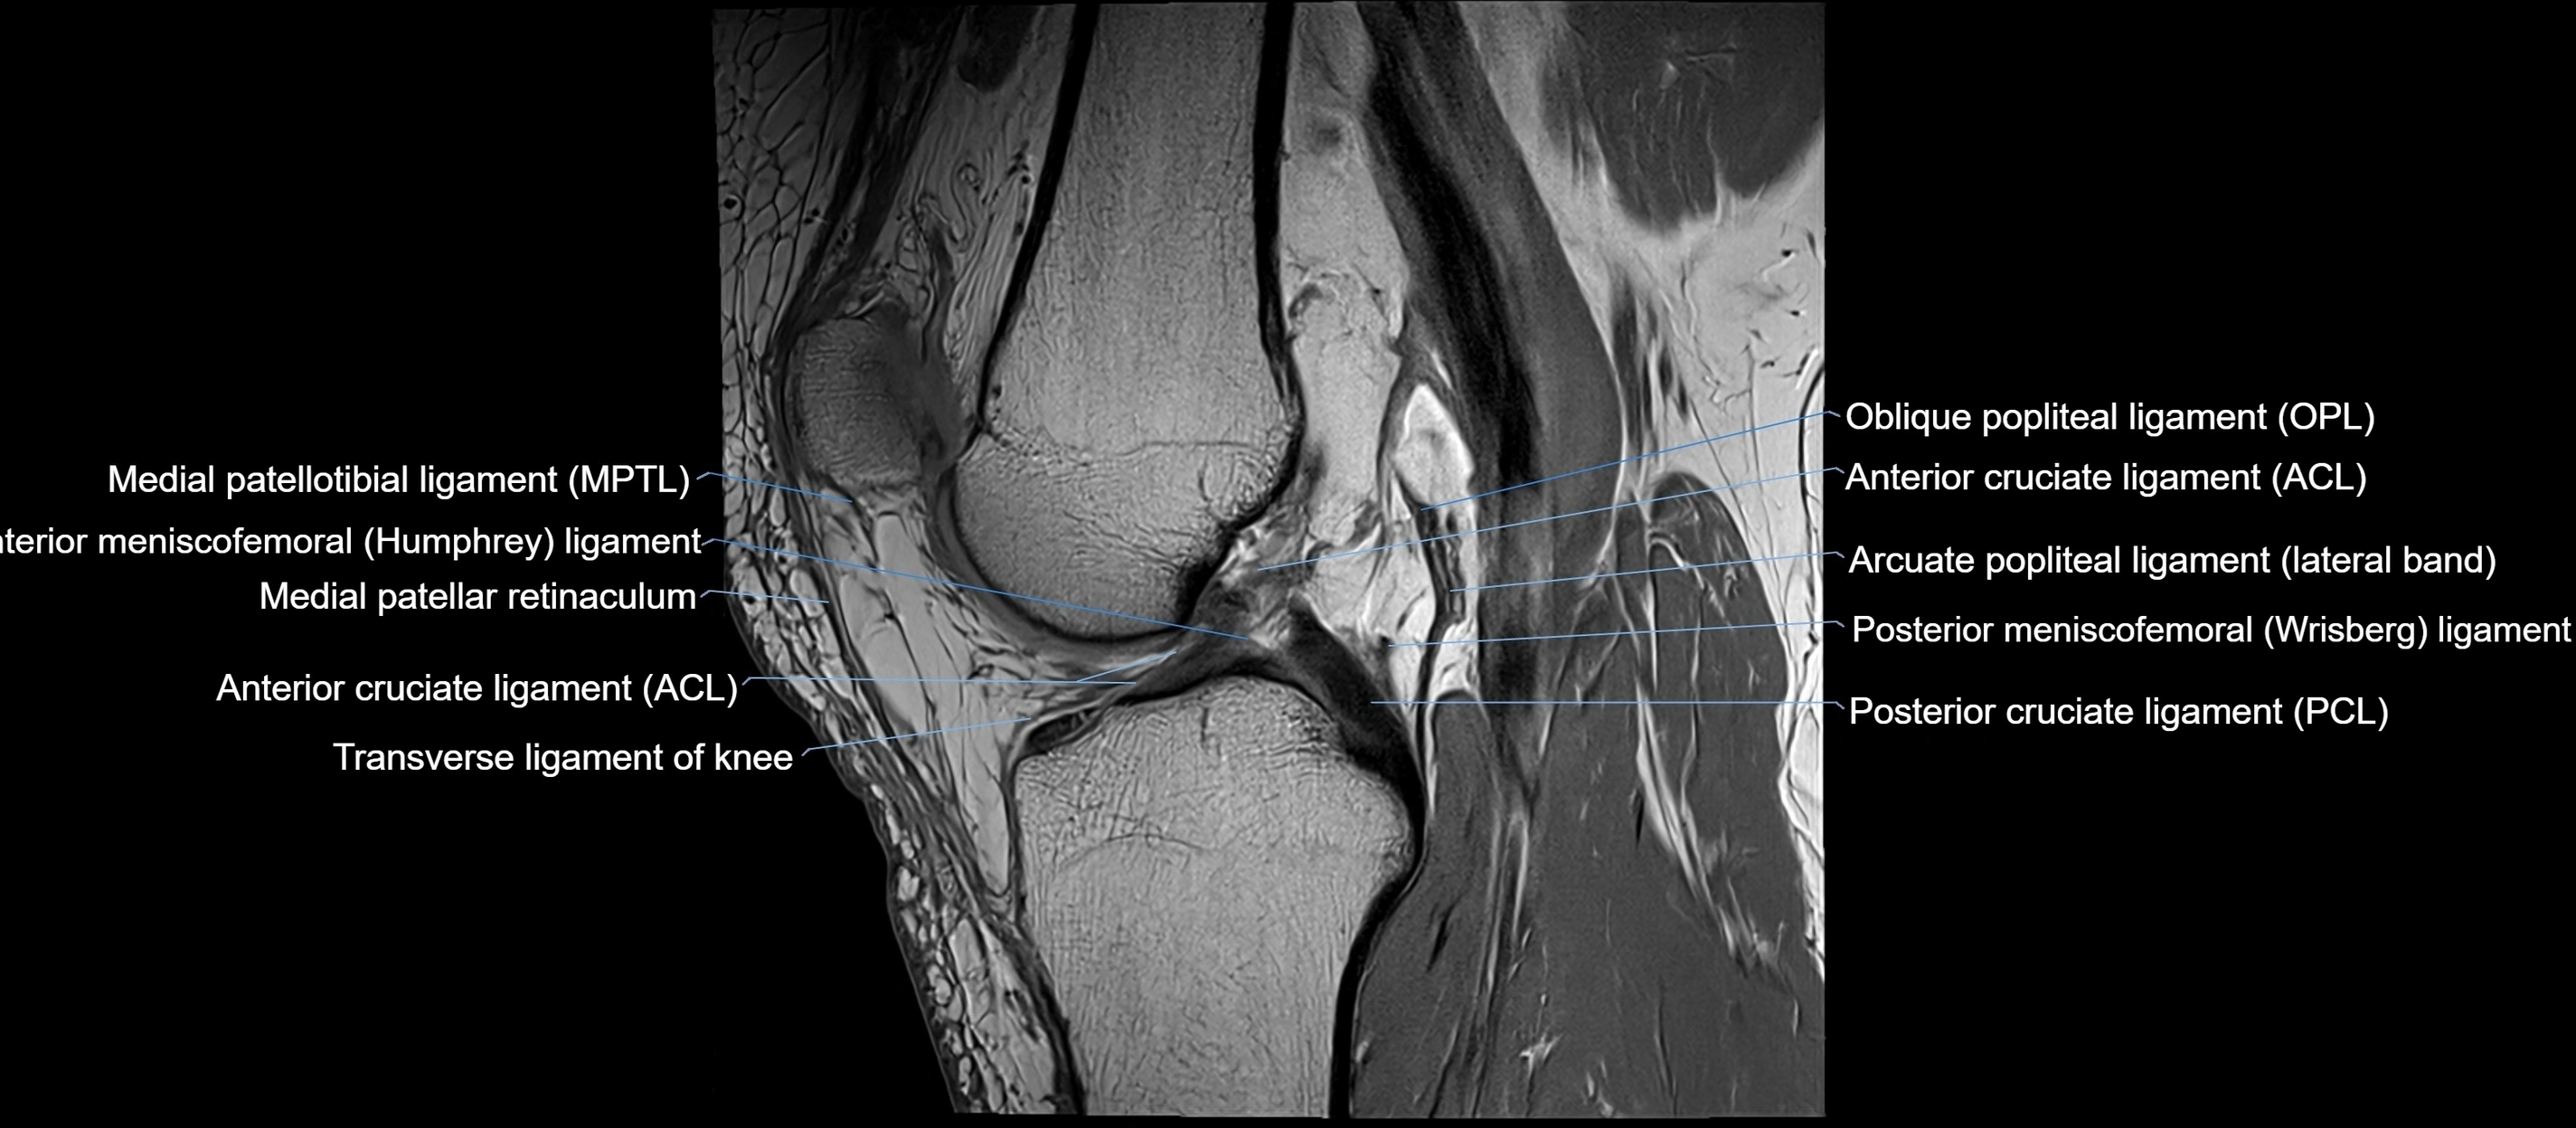

MRI images

image